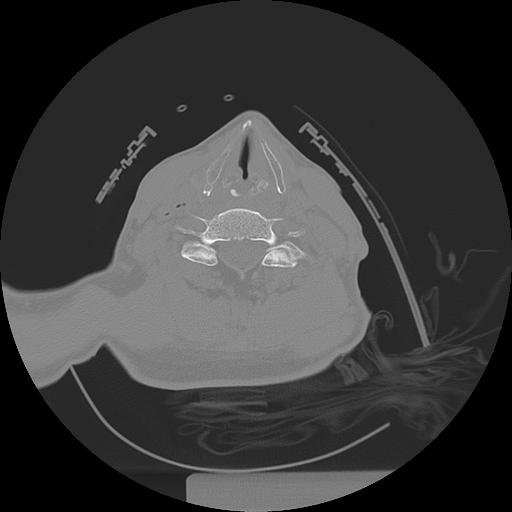

11 HUESO,,Axial,2.0,HUESO,,